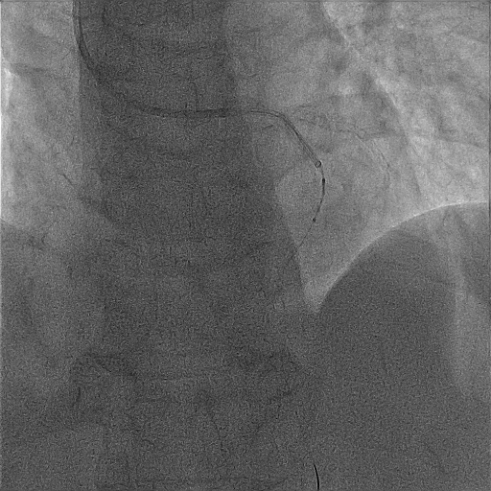

经2.5mm*15mm球囊预扩处理后,在Guidezella延长导管支撑下,将谱创医疗Sonico-CX 2.5mm*12mm冲击波球囊送至前降支中段,经过40次冲击波(4个周期,每个周期分别以4atm激发冲击波,再以8atm扩张成形)处理后,成功碎裂钙化斑块。

Guidezella延长导管支撑下,冲击波球囊送至前降支中段钙化处

冲击波球囊处理前降支钙化病变